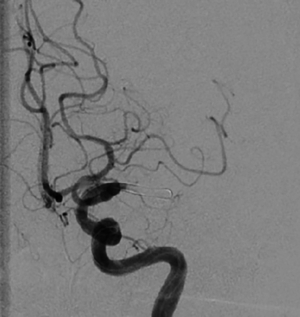

b) Wiedereröffnetes Gefäß nach Thrombektomie in Solumbra-Technik

Der Einsatz eines Stentretrievers ist die bisher am häufigsten eingesetzte Technik. Hierbei handelt es sich letztlich um einen modifizierten intrakraniellen Stent, der an einem 0,014-inch-Draht befestigt ist. Der Thrombus wird mit einem 0,014-inch-Mikrodraht und einem 0,021-inch-Mikrokatheter passiert. Über den Mikrokatheter wird der Stentretriever im Thrombus freigesetzt, der Blutfluss nach distal ist jetzt wiederhergestellt. Nach einer Wartezeit von 5–8 Minuten, in der sich der Thrombus in den Stentmaschen festsetzen soll, wird der Stentretriever entfaltet zurückgezogen. Damit der Stentretriever ohne Abscheren des Thrombus in der langen Schleuse geborgen werden kann, muss eine Schleuse mit abschraubbarem Ventil verwendet werden. Bei der Adapt-Technik (direct aspiration first-pass thrombectomy) wird ein großlumiger Aspirationskatheter direkt vor den Thrombus gebracht, bei einem Verschluss der proximalen A. cerebri media wird dazu ein 6F-Katheter verwendet. Über eine Aspirationspumpe wird dann der Thrombus in den Katheter gesaugt. Nach frühestens 90 s wird, falls der Thrombus nicht komplett aspiriert werden kann, der Aspirationskatheter unter Sog mit dem Thrombus an der Katheterspitze zurückgezogen. Bei der Solumbra-Technik, benannt nach ihrem Erstbeschreiber, wird ein Stentretriever-Manöver mit einem Aspirationskatheter, der bis an den Thrombus herangeführt wird, kombiniert. Eine Weiterentwicklung der Solumbra-Technik ist die SAVE-Technik (stent retriever assisted vacuum-locked extraction). Der Stentretriever wird zu 2/3-Dritteln distal des Thrombus freigesetzt. Hierdurch wird ebenso wie durch das Rückholen in einen Aspirationskatheter das Risiko einer distalen Embolisation verringert.